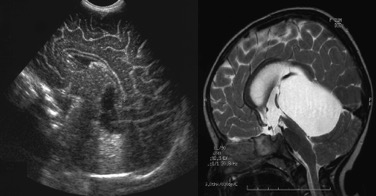

la malformation de Dandy-Walker

il s’agit d’une malformation due à l’imperforation de la toile choroïdienne du V4, qui soulève de façon caractéristique le vermis cérébelleux.

le pronostic est incertain ; les éléments de pronostic défavorable sont :

- l’existence d’une hydrocéphalie évolutive, avec dilatation ventriculaire et tronc cérébral plaqué en avant

- l’hypoplasie du cervelet

- le contexte malformatif (syndrome PHACE)